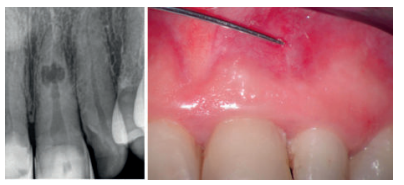

Nos refieren a la consulta una mujer de 60 años, sin antecedentes médicos de interés, que sufrió un traumatismo con anterioridad, aunque no recuerda la fecha con exactitud. Presenta ligeras molestias a nivel gingival y sostiene que sufrió episodios de inflamación y dolor. A la inspección intraoral presenta una fístula o trayecto sinusal a la altura del 21 y unas carillas de composite desgastadas en el sector antero-superior. Las pruebas diagnósticas realizadas sobre el diente 21 indican la ausencia de vitalidad y percusión vertical, palpación positiva y sondaje-movilidad fisiológica. Los dientes 11 y 22 se encontraban asintomáticos y con vitalidad positiva normal.

Tras realizar una radiografía periapical (Figura 1) se puede observar un ensanchamiento de forma ovalada a la altura del tercio medio del conducto del diente 21, que puede corresponderse con una reabsorción. Ante este hallazgo radiográfico, se decide realizar una prueba complementaria mediante CBCT (CS 8100, Carestream Dental, Atlanta, Estados Unidos) para comprobar la extensión de la lesión y si ésta es o no perforante.

Se realiza un CBCT de campo pequeño con un voxel de 75 micras. A través de las pruebas complementarias, estudio radiográfico y análisis de la literatura llegamos al diagnóstico de reabsorción interna inflamatoria perforante (Figura 2).